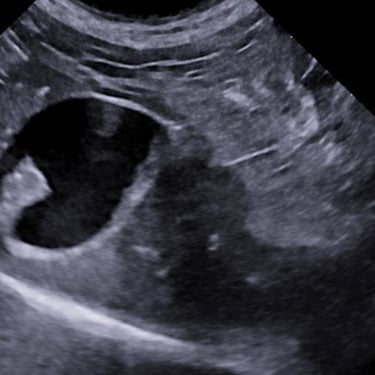

Practicing companion animal veterinary medicine in Simcoe County since 2012, Dr. Elyse is experienced in a variety of clinical settings from emergencies to chronic disease management and routine care.

Focusing on efficiency, workflow, and accuracy to provide actionable information to pet parents and veterinarians, while keeping patient wellbeing at the forefront.

Dr. Hauer has completed over 270 formal hours of continuing education in diagnostic abdominal and cardiac ultrasound from a variety of experts in the field, including a year-long immersive Advanced Imaging program through the Academy of Veterinary Imaging in Arlington, TX. She is a member of the International Veterinary Ultrasound Society.

Pearls of GIT/Adrenals Ultrasound Course - Scil Vet Novactions (7.5 hours), 2014

Sonopath Sonographic Diagnostic Efficiency Protocol - The Everything Lab + Ortho, 2023 (22 hours)

FASTVET: Certificate of AFAST® Course Completion (8 hours), 2025